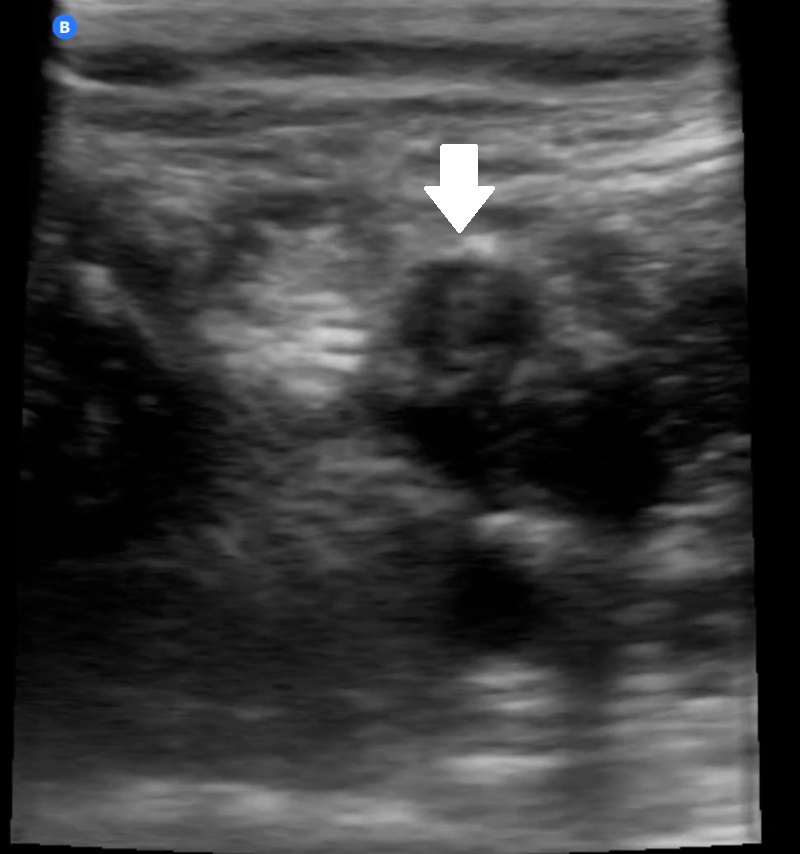

Hallazgos ecográficos

Consolidación con broncograma aéreo de 4 x 2 cm en campo posterolateral inferior derecho con leve derrame pleural adyacente al diafragma, y líneas B alrededor de la consolidación (imagen 2).